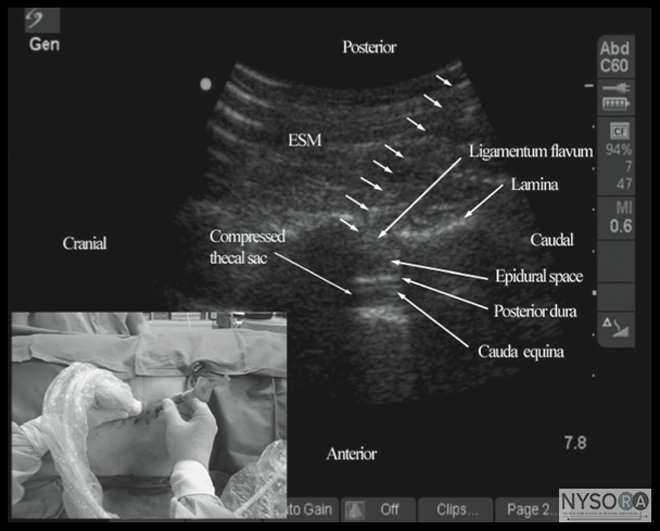

Figure 13: Transverse sonogram of the lumbar spine with the transducer positioned such that the ultrasound beam is insonated through the interspinous space (i.e., transverse interspinous view). The epidural space, posterior dura, intrathecal space, and the anterior complex are visible in the midline, and the articular process (AP) is visible laterally on either side of the midline. Note how the articular processes on either side are symmetrically located. Picture in the inset shows a corresponding computed tomography (CT) scan of the lumbar vertebra. The CT slice was reconstructed from a three-dimensional CT data set from the author's archive. ESM, erector spinae muscle; ES, epidural space; PD, posterior dura; ITS, intrathecal space; AC, anterior complex; VB, vertebral body. Karmakar and colleagues recently described a technique of real-time, US guided epidural injection in conjunction with loss of resistance (LOR) to saline. (17) The epidural access was performed by a single operator, and the epidural needle was inserted in the plane of the US beam via the paramedian axis. (17) Generally, it is possible to visualize the advancing epidural needle in real time until it engages in the ligamentum flavum. (17) The need for a second operator to perform the LOR can be circumvented by using a spring-loaded syringe (e.g., Episure AutoDetect syringe, Indigo Orb, Inc., Irvine, CA, USA), with an internal compression spring that applies constant pressure on the plunger (Figure 18). (17) Anterior displacement of the posterior dura and widen- ing of the posterior epidural space are the most frequently visualized changes within the spinal canal. Compression of the thecal sac can be seen occasionally. (17) These ultrasonographic signs of a correct epidural injection were previously described in children. (35) The neuraxial changes that occur within the spinal canal following the "loss of resistance" to saline may have clinical significance. (17) Despite the ability to use real-time US for establishing epidural access, visualization of an indwelling epidural catheter in adults proved to be more challenging. Occasionally, anterior displacement of the posterior dura and widening of the posterior epidural space after an epidural bolus injection via the catheter can be observed and can be used as a surrogate marker of the location of the catheter tip. Grau and colleagues postulated that this may be related to the small diameter and poor echogenicity of conventional epidural catheters. (15) It remains to be seen whether or not the imminent development of echogenic needles and catheters will have an impact on the ability to visualize epidurally placed catheters.

Figure 18: Paramedian oblique sagittal sonogram of the lumbar spine showing the sonographic changes within the spinal canal after the "loss of resistance" to saline. Note the anterior displacement of the posterior dura, widening of the posterior epidural space, and compression of the thecal sac. The cauda equina nerve roots are also now better visualized within the compressed thecal sac in this patient. Picture in the inset shows how the Episure AutoDetect syringe was used to circumvent the need for a third hand for the 'loss of resistance'. Today, there are several models (phantoms) for practicing US-guided central neuraxial interventions. The "water-based spine phantom" (18) is useful for learning the osseous anatomy of the spine, but it is not a good model for learning US-guided spinal interventions because it lacks tissue mimicking properties. Spinal and paraspinal sonography is often taught at workshops, but they are not suitable for prac- ticing actual techniques. Fresh cadaver courses are available, and they allow participants to study the neuraxial sonoanatomy and practice US-guided CNB with realistic haptic feedback, but they may be limited by the quality of the US images. However, such courses are uncommon and conducted in anatomy departments with the cadavers in a position that rarely mimics what is practiced in the operating room. Anesthetized pigs can also be used, but animal ethics approval is required and, for the organizers, a license from the local health department to conduct such workshops. They entail infectious precautions, and religious beliefs may preclude its use as a model. Moreover, such workshops are conducted in designated animal laboratories that are typically small and not suited to accommodate large groups of participants. To circumvent some of these problems, the group at the Chinese University Hong Kong recently introduced the "pig carcass spine phantom," (Figure 4), (19) an excellent model that can be used in conference venues and provides excellent tactile and visual feedback. (19) The limitation of the "pig carcass spine phantom" is that it is a decapitated model and there is loss of cerebrospinal fluid during the preparation process. This presentation results in air artifacts and loss of contrast within the spinal canal during spinal sonography unless the thecal sac is cannulated at its cranial end and continuously irrigated with fluid (normal saline), a process that requires surgical dissection to isolate the thecal sac. Therefore, an "in vitro" model that can facilitate the learning of the scanning techniques and the hand-eye coordination skills required for real-time US-guided CNB is highly desirable. A low-cost gelatin-based US phantom of the lumbosacral spine recently was proposed. (44) However, the gelatin phantom is soft in consistency, lacks tissue-mimicking echogenic properties, does not provide a haptic feedback, is easily contaminated with mold and bacteria, and needle track marks limit its usefulness, (44) all of which preclude its extended use. Karmakar and colleagues recently developed a "gelatin-agar spine phantom" that overcomes some of the drawbacks of the gelatin-based spine phantom. It is mechanically stable, has a tissue-like texture and echogenicity, needle track marks are less of a problem, and it can be used over extended periods of time to study the osseous anatomy of the lumbosacral spine and to practice the hand-eye coordination skills required to perform US-guided CNB. (45)